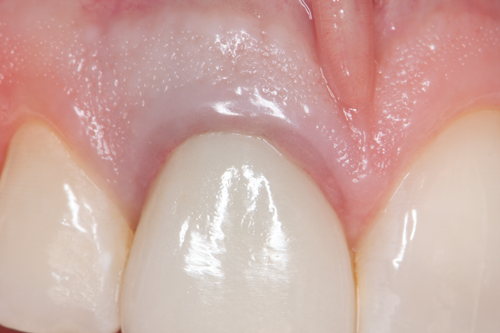

Fig 4. A maxillary right central incisor was restored with a cast-metal post, which can result in discoloration and shadowing of the gingiva and cervical aspect of the tooth. The incidental light was completely blocked by the metal post and underlying metal framework of the crown, which caused a characteristic shadow at the submarginal zone.

Figure 4